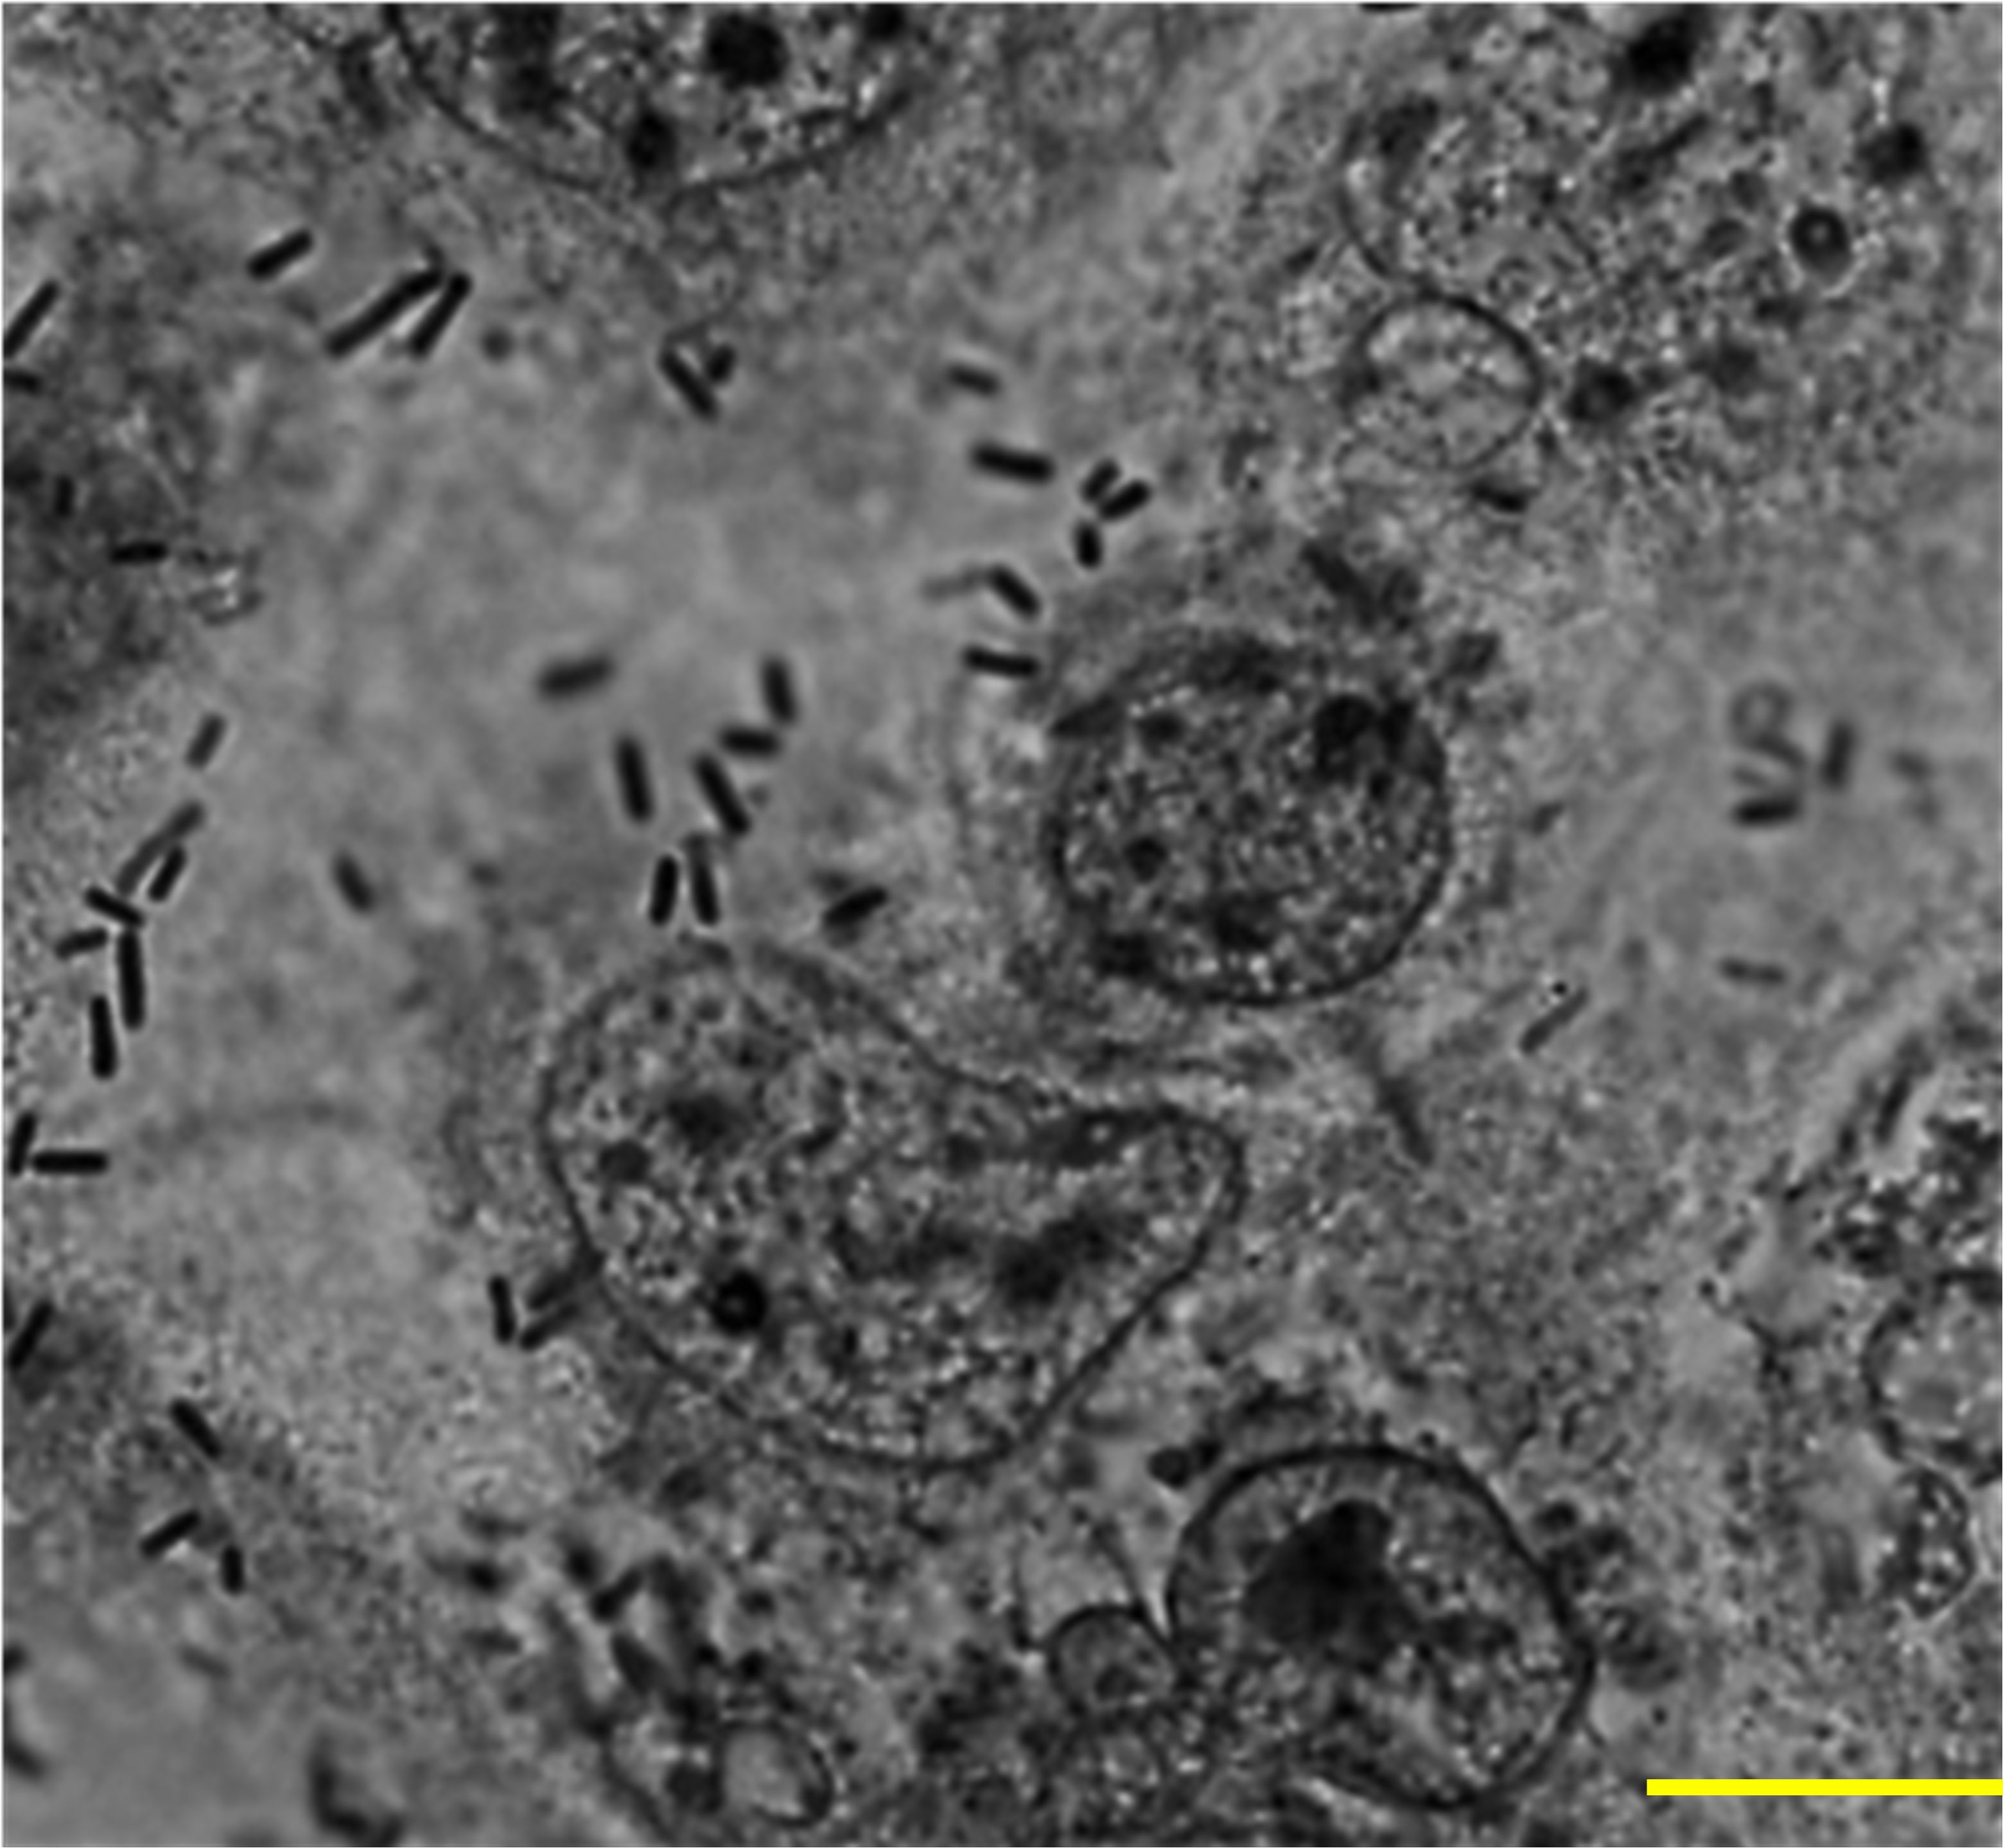

Adherence of L. plantarum to caco-2 epithelial cells

L. plantarum exhibited characteristic compact and diffuse adherence to Caco-2 epithelial cells (Figure 1). Quantitative analysis revealed an average bacterial attachment of 5.65 ± 1.18 bacteria per epithelial cell. L. plantarum activates vacuolation and grows in murine macrophages.

Figure 1. Adherence of L. plantarum to Caco-2 epithelial cells. A subconfluent monolayer of Caco-2 epithelial cells were challenged with L. plantarum at a multiplicity of infection of 1:100 at 37°C, 5% CO2 for 2 h and epithelial cells were stained with Giemsa stain. A total of 100 cells were examined under a light microscope, and the number of bacteria adhering to each cell was counted in 20 randomly selected fields. The number of attached L. plantarum per Caco-2 cell was 5.65 ± 1.18. Images were acquired via phase contrast microscopy (BX-43, Olympus Co., Tokyo, Japan). Scale bar, 10 µm.

In this study, L. plantarum exhibited a strong and consistent attachment to Caco-2 cells, forming a distinct adherence pattern. Quantitative evaluation revealed an average of 5.65 bacterial cells adhering per epithelial cell, indicating strong colonization potential. These findings support previous observations that effective bacterial adhesion is central to reducing pathogen establishment and maintaining intestinal microbial balance (1, 38).